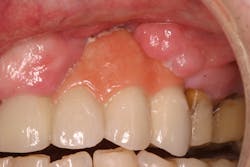

Reduction in quantity and quality of bone can also compromise functional and esthetic outcomes of both implants and fixed bridge restorations (figures 3 and 3a).

• Site development to increase hard and soft tissue for pontic sites in fixed bridge prosthetics (figures 4–4e)